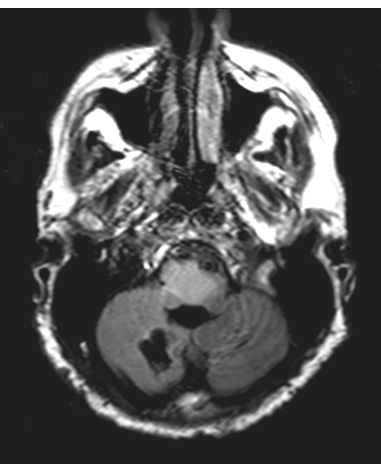

Case 3 History ---- The patient is a 46-year-old man with a clinical history of neurofibromatosis 1, epilepsy disorder, and multiple supratentorial and large pontomedullary FLAIR hyperintense masses with ring enhancing components in the right pons. Imaging is also significant for ventriculomegaly, with absence of associated symptoms. Operative procedure: Brain biopsy ---- 3A1 There is a hyperintense brainstem and cerebellar tumor as shown by this FLAIR MRI scan.